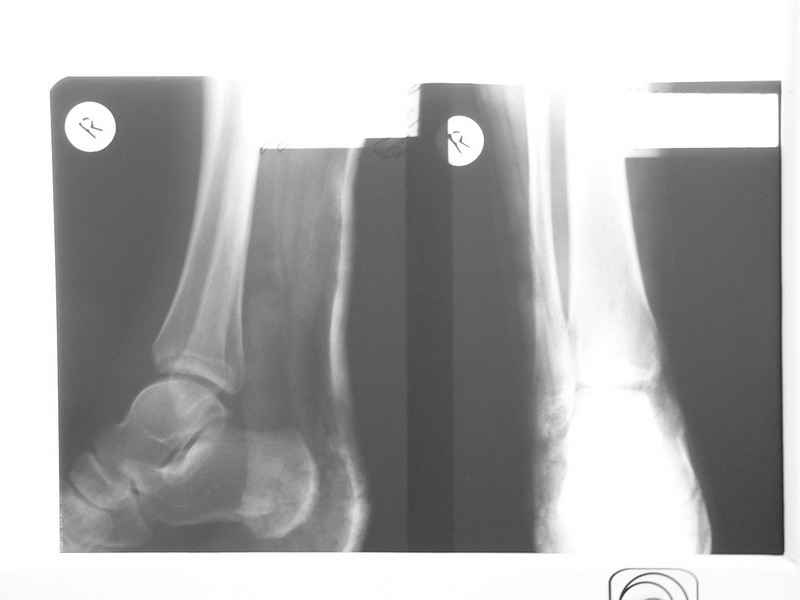

Re: Остеомиелит медиальной лодыжки

Нашел в архиве форума снимки от 2007 года. Классная штука интернет! Александру Николаевичу отдельное спасибо!